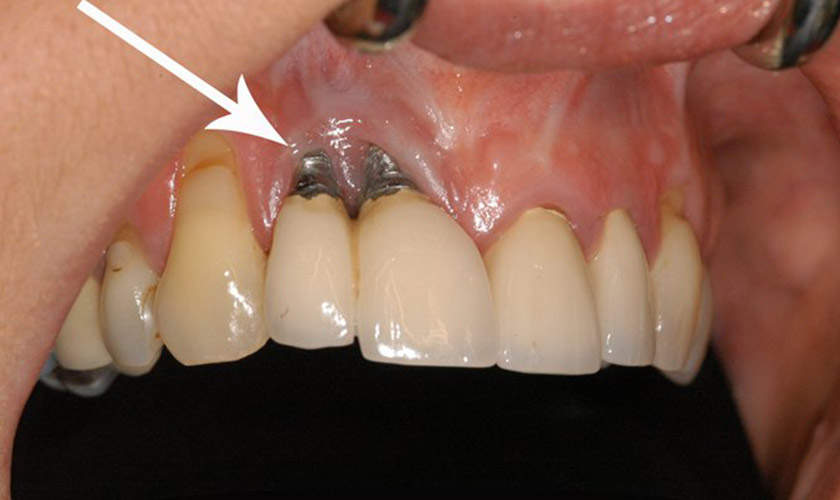

Viêm quanh Implant là một trong những biến chứng sau cấy ghép trụ Implant mà bệnh nhân có thể gặp phải với những biểu hiện như: sưng, đau, chảy máu, hình thành túi mủ quanh khu vực cấy ghép răng, hôi miệng, tụt nướu, trụ Implant bị lung lay...

Viêm quanh Implant là một biến chứng nguy hiểm, có thể dẫn đến tình trạng đào thải trụ Implant

Viêm quanh Implant xảy ra khi màng sinh học hình thành quanh Implant, tạo điều kiện cho vi khuẩn tấn công vùng răng vừa cấy ghép và gây viêm nhiễm, dẫn đến tình trạng xương nâng đỡ quanh Implant bị phá hủy, không thể nâng đỡ trụ Implant và làm đào thải trụ.